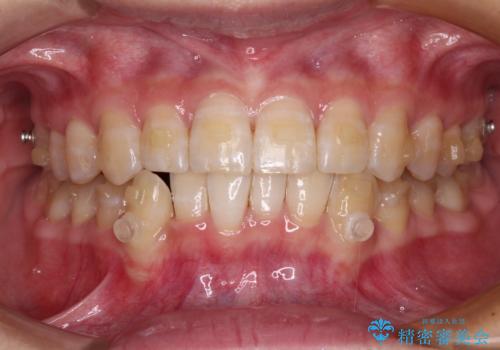

- 下顎の八重歯を気にして来院された患者様です。

マウスピース矯正でもワイヤー矯正でも対応可能であり、マウスピースによる治療を希望されたため、インビザラインを用いることとしました。

下顎前歯にデコボコが集中していたため、顎間ゴムによる後方移動とIPR(歯と歯の間を削ること)により歯列を整えることとしました。

下顎前歯のデコボコが集中しており、奥歯の咬み合わせは、上顎に対して下顎が前方位にある状態でした。下顎の歯列を後方へ移動させる治療はインビザラインの得意とするところですので、1年程度で無事に治療を終えることができました。